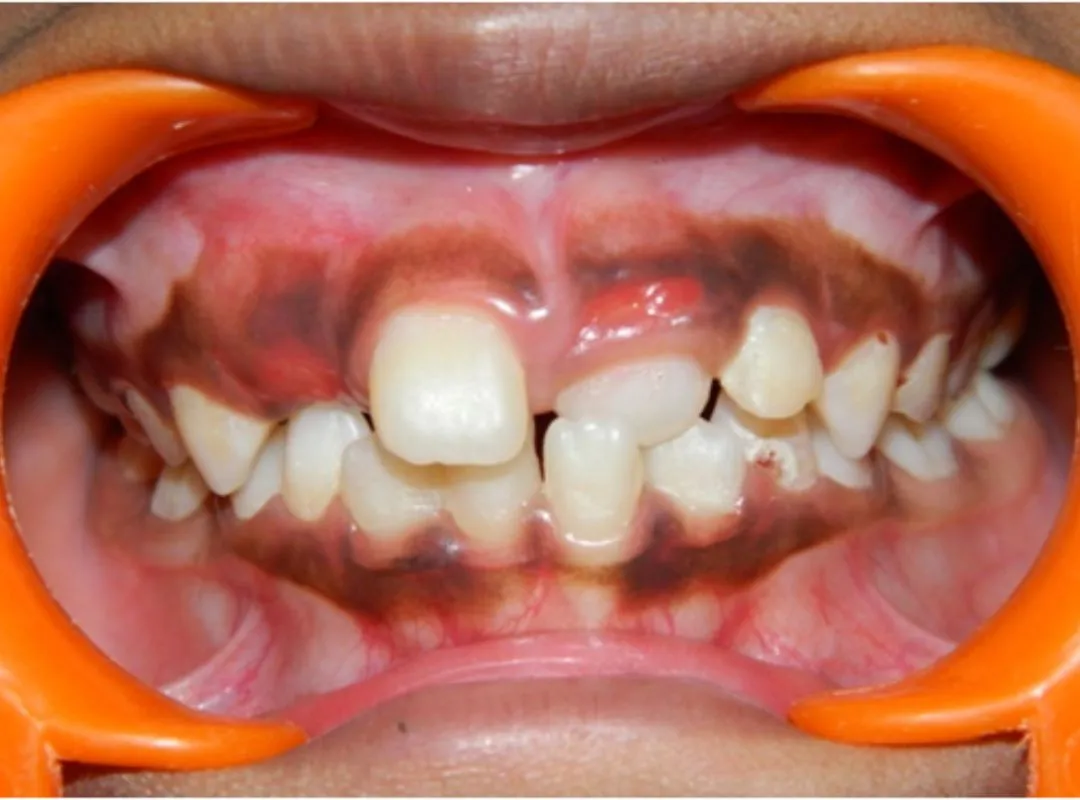

Pediatric Dentistry Gentle, safe, child-friendly care that ensures kids feel safe, comfortable, and confident.

Yes If you're looking for a dental clinic in that’s friendly with kids or convenient for families. JP Dental provides dental care for the entire family, including children, adults, and seniors. We create a friendly and comfortable environment so children and first-time patients feel at ease during their visit., you're in the right place. We try to make the experience light and stress-free, especially for little ones who might be nervous. You can even book appointments together as a family if that works better. We believe dental care should be comfortable for all age groups from toddlers to grandparents.